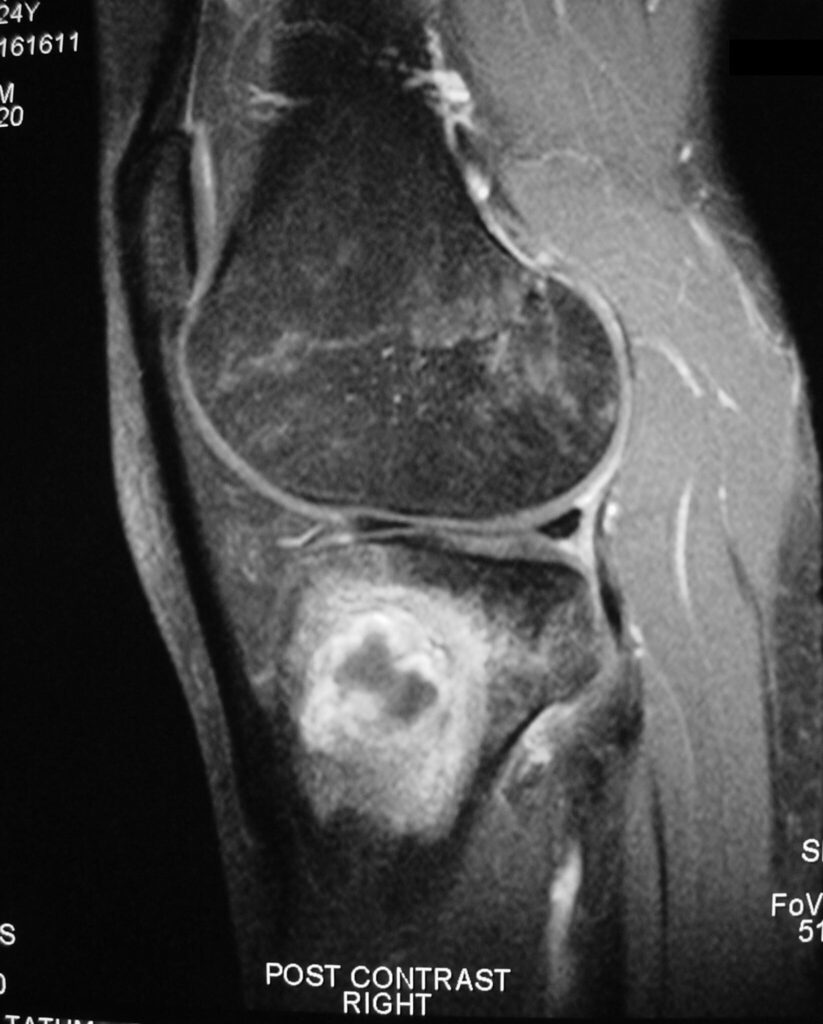

MRI (Fig. 4-7)

• Central low signal intensity with peripheral enhancement on T1-weighted images

• Heterogeneous high signal intensity with low signal in surrounding sclerotic bone on T2-weighted images

Fig. 4

Fig. 5

Fig. 6

Fig. 7

Fig. 4-7: MR imaging of a benign fibrous histiocytoma of the proximal tibia demonstrates a heterogeneous high signal intensity and low signal intensity with surrounding sclerotic bone on T2-weighted images. T1-weighted images show low signal intensity. No soft tissue mass is visible.